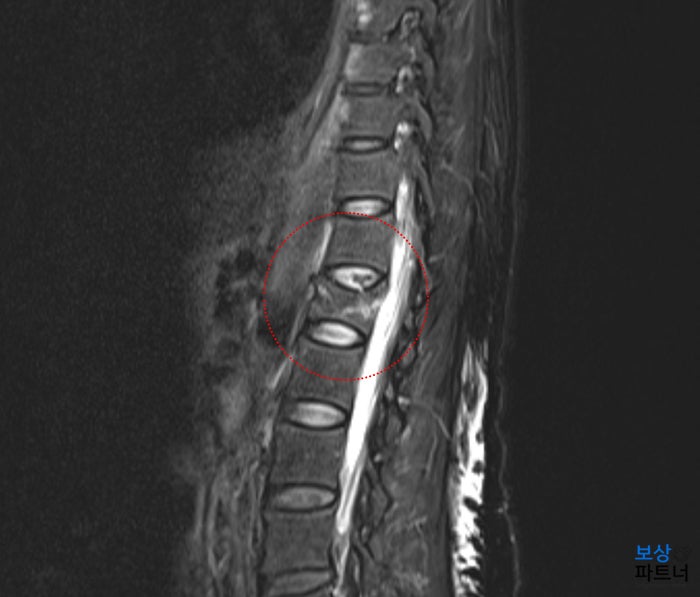

흉추 9번 부위의 골절 [질병분류코드 S2206]

장해 지급률을 인정받기 위해서, 전문의로부터'후유장해 진단서'를 받아야 하는데요. 보험금 지급심사의 중요한 근거가 되기 때문에 제대로 발급받는 것이 무엇보다도 중요합니다. 흉추 골절의 경우 수술을 받지 않았더라도 골절 자체만으로도 보험약관상 후유장해 요건에 해당됩니다. (척추의 기형장해) 그리고 척추의 기형장해는 콥스각 측정방식(척추체의 기울기 변형) 또는 압박률 측정(척추체가 내려앉은 정도)하여 더 유리한 쪽으로 진단을 받아야 합니다.